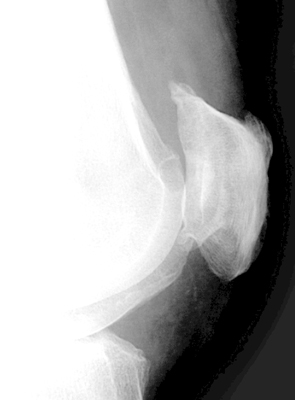

Enthesopathy of the patella at the attachment of the quadriceps tendon on the axial view of the patella (sunrise view) resemble teeth.

Sunrise view - Click on the image for a larger versionALateral Knee - Click on the image for a larger versionB